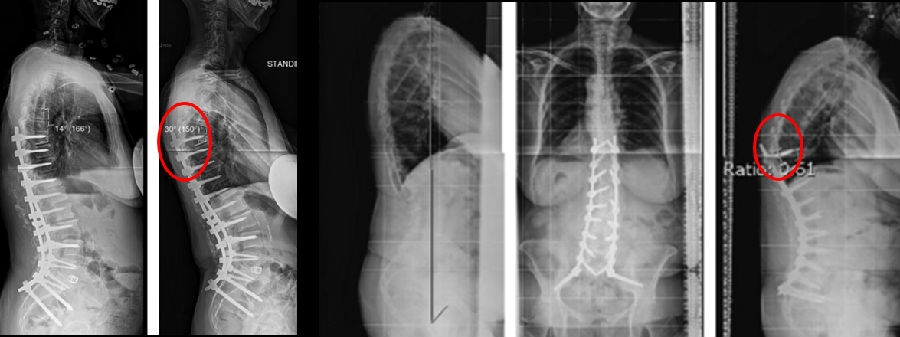

Ø 术后PI-LL不匹配,PI-LL大于10°

图21 术后PI-LL不匹配,大于10°